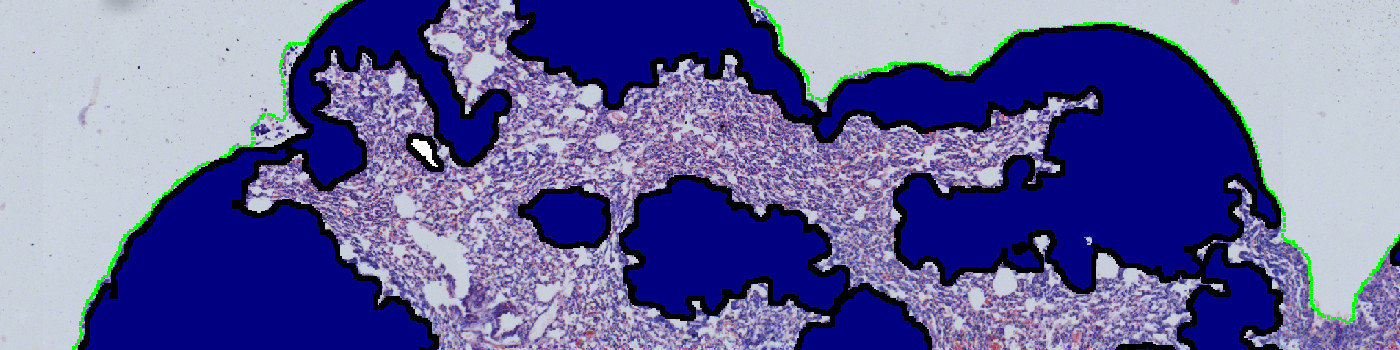

This protocol can be used to quantify metastases in H&E stained lung sections. The APP detects the total area of the lung tissue, delineates and separates the metastases and quantifies the area for each metastatic nodule. In the end, the total tissue area, the number of metastases, the area of each metastasis and the metastatic area percentage are given.

Step 2: Load the APP for metastases detection “02 Metastasis Detect” which identifies the metastases inside the lung tissue.

The first image processing step involves a segmentation of the lung tissue (see FIGURE 1). Afterwards the metastases are identified together with the regions that are either too misshaped, too red or too sparse for being identified as metastases (see FIGURE 5). The parameters defining the shape and sparseness of the metastases can easily be adjusted by the user.